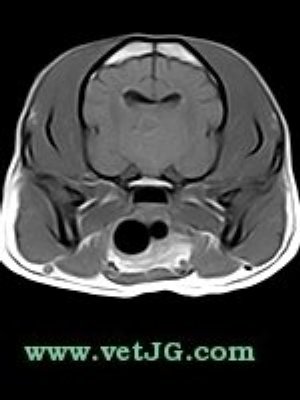

RESONANCIA MAGNÉTICA

AXIAL